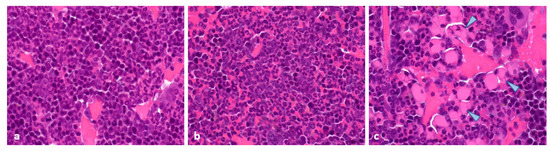

In all sampled tumours, SST2 expression, which was primarily localised to the cell membrane, was very strong (H-score of 300) independently of the administered treatments (vehicle, [177Lu]Lu-satoreotide tetraxetan, or [177Lu]Lu-DOTA-TATE at any dose) (Figure 3).

Figure 3. Somatostatin receptor subtype 2 (SST2) expression in tumours. The basal high SST2 expression (a) was not modified by the administered treatments either with [177Lu]Lu-DOTA-TATE (b) or [177Lu]Lu-satoreotide tetraxetan (c) 96h post last administration. All images were taken using an objective 40.